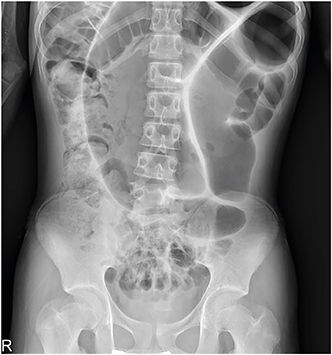

A previously healthy 16-year-old boy with stable vital signs presented with vomiting, diarrhea, distension, and abdominal pain for 4 days. On physical examination, he had abdominal distension with mild abdominal tenderness but without rebound tenderness, and a subtle metallic bowel sound. Laboratory test results were normal. An abdominal radiography revealed a dilated sigmoid colon on the left quadrant (Fig. 1). An abdominal computed tomography (CT) revealed a marked distension of the gas-filled sigmoid colon with twisting of the mesenteric vessels, confirming SV (Fig. 2). A rectal tube was inserted to decompress the volvulus (Fig. 3). He remained asymptomatic thereafter, and discharge was requested. At 2 and 7 months after his initial attack, he was readmitted to the emergency department with the same complaints. Subsequent examinations confirmed the recurrence of SV. The SV was successfully decompressed by means of a rectal tube. His parents again refused surgical treatment; however, 9 months after the first attack, he underwent laparoscopic-assisted sigmoid colectomy. We use a 12 mm port above the umbilicus, a 5 mm right upper quadrant port, a 5 mm left sided port, and a 12 mm right lower quadrant port & left lower quadrant, typically placed 2 fingerbreadths medial and 2 fingerbreadths cephalad to the anterior superior iliac spine. After mobilization of the sigmoid colon, the colon was transected at the rectosigmoid junction with an endolinear stapler (SigniaTM Stapling System; Medtronic, Minneapolis, MN, USA). The umbilical incision was extended. The divided sigmoid colon was exteriorized, and the redundant part was resected. A sigmoid colon section of 34 cm was resected; end-to-end colorectal anastomosis was performed intracorporeally using a circular stapler (ECHELON CIRCULARTM 25 mm Powered Stapler; Ethicon, Bridgewater, NJ, USA). A seromuscular biopsy specimen from the distal colon submitted for histopathologic examination showed normal ganglion cells. On postoperative day 3, he was started on water intake; subsequently, eating progressed successfully. He was discharged without complications on postoperative day 10.

Fig. 3

Abdominal X-ray showing decompression of the volvulus by means of a rectal tube (arrow).